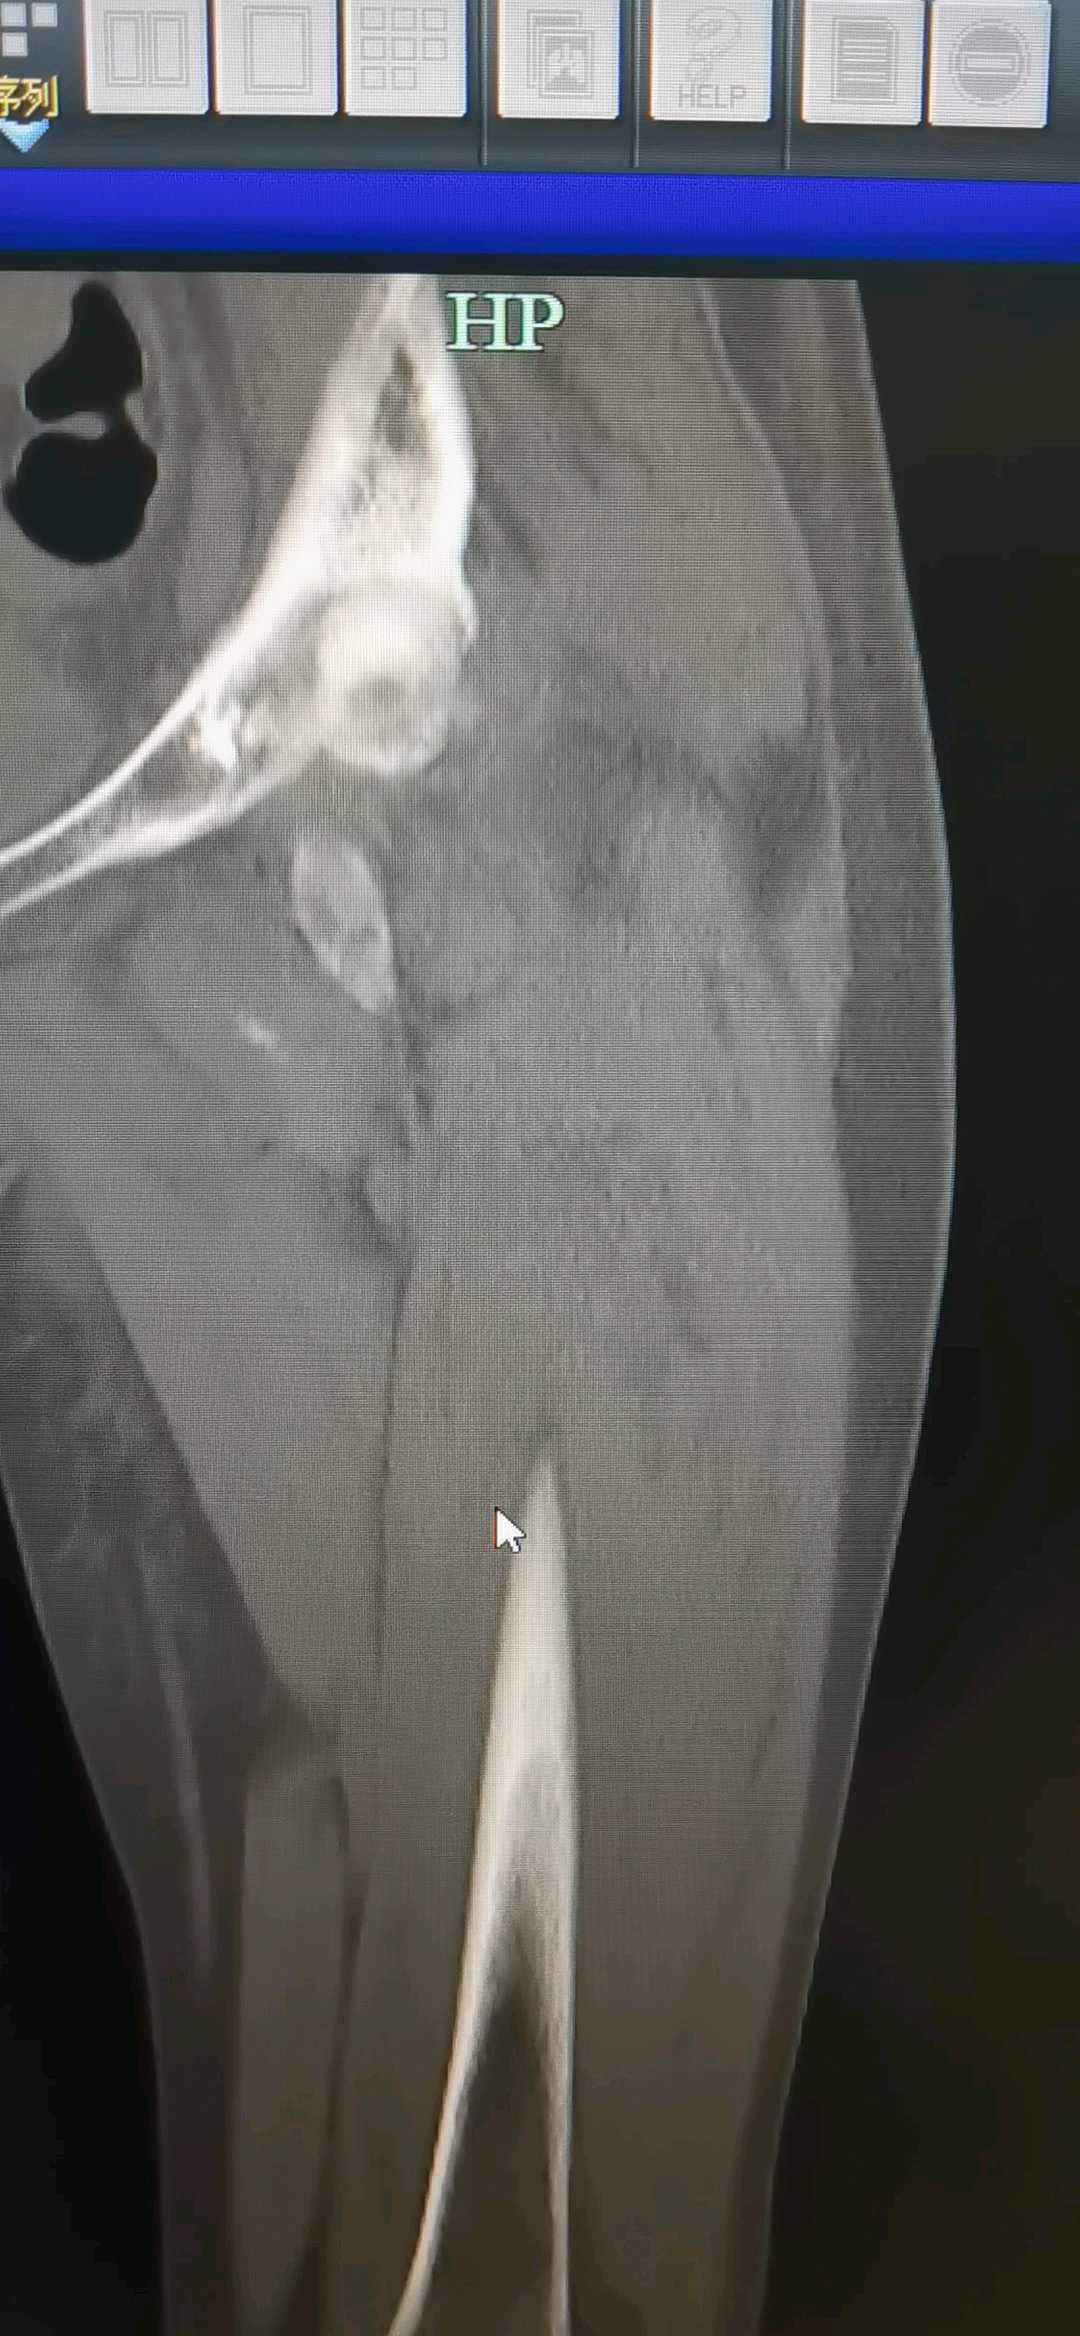

转子下的,头段和干总是会张嘴,想通过头颈钉拉回来的想法不太可取。(至少骨折间隙不是平行的那种)

这次用血管钳抵了一把,本来朝下的导针,朝向股骨头圆心。避开之前术后残留的坏死区域(也不知道里面塞了啥东西,既往病史不详)。

这次感受了绞锁的两枚钉长度的选择。上面那枚打算加压多少(看骨折间隙,对应红线和不同的三条黄线),下面这枚计算长度的时候,要把这个间隙考虑进去,然后下面这枚拧进去的时候,上面那枚会后退,从而形成加压,缩小间隙。长钉的钉尾要减少刺激,长度要预估好。

另外,下面短钉(长度一般要短于上面的),有时候可以和上面一样长。